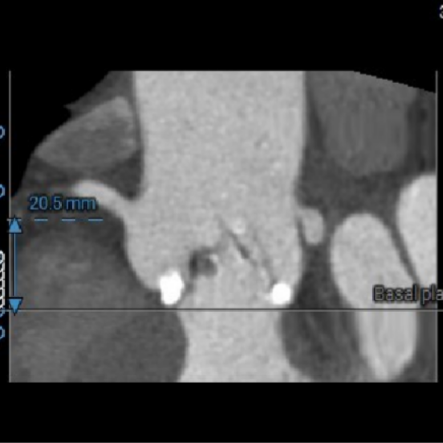

● 主动脉瓣环水平夹角46度,非横位心,主动脉弓角度宽度尚可;

虚拟瓣环与水平夹角

图片